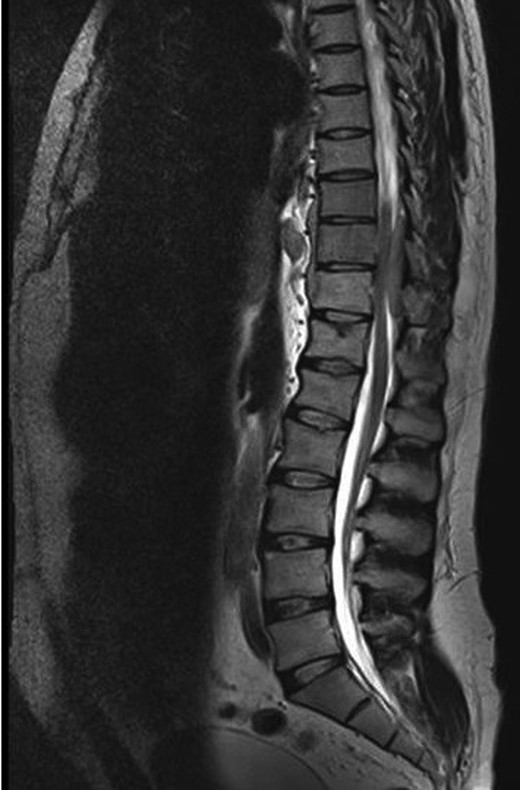

A 30-year-old male patient was admitted to our clinic with back pain. Pain was provoked by movements. The severity of pain was associated with the inability to perform the activities of daily living. The patient did not have any lymphoma-related B-type symptoms, including body weight loss, fever and sweat at night. He did not have a past and family history. There was no neurological deficit. Routine laboratory test results were normal. A magnetic resonance imaging (MRI) scan of the thoracic spine demonstrated an epidural tumor at the T9–11 level (Figs 1–3). The patient underwent spinal cord decompression via total laminectomy of T9–11 levels. Subtotal resection of the tumor was performed. Histological examination revealed the polymorphous cellular infiltration by histiocytes, large mononuclear cells and lacunar Reed–Sternberg cells with folded multi-lobed nuclei and small nucleoli (Fig. 4). Immunohistochemical staining was positive for CD15 and CD30 and negative for CD3, CD20, CD79a or CD45Ro. These features were most frequently observed in the mixed cellularity type of Hodgkin's lymphoma. Histological examination of the vertrebral body revealed no abnormality. The results of all other examinations (F-18 fluorodeoxyglucose positron emission tomography (F-18 FDG PET/CT), bone marrow biopsy and computed tomography (CT) of the chest, abdomen and pelvis) were negative for an occult disease. The patient was referred to the hematology department to undergo staged treatment. Six courses of chemotheraphy containing ABVD regimen (adriamycin, bleomycin, vinblastine and dacarbazine) were given to the patient. Postoperative MRI scan did not reveal any evidence of Hodgkin's disease (Fig. 5), F-18 FDG PET/CT, CT of the chest, abdomen and pelvis were obtained in 24 months and did not reveal any evidence of Hodgkin's disease.

Postoperative MRI scan did not reveal any evidence of Hodgkin's disease.

Moridaira et al. [4] reported a case of Hodgkin's disease at T8–10 epidural space. Rao et al. [6] published a case with primary spinal epidural Hodgkin's lymphoma. Our case is apparently the seventh case to be diagnosed with Hodgkin's disease who presented with spinal cord compression due to epidural space without lymphoma elsewhere. The abnormal MRI marrow signal of the T9 and T10 vertebral bodies can be seen in Fig. 5. Maybe the tumor in fact originated within the abnormal T9 or T10 bone marrow and spread to the epidural space via the epidural venous plexus. But histological examination of the vertebral body revealed no abnormality.